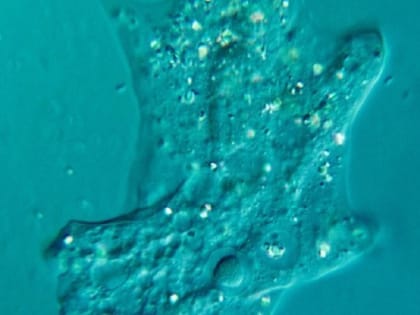

В Индии амеба проникла в мозг подростка и убила его

Панавалли. Индия. 15-летний житель Индии умер в результате заражения головного мозга амебами.